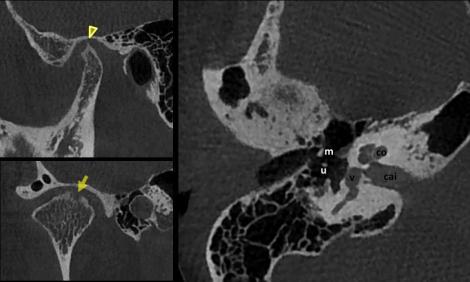

Le niveau de qualité d’image en CBCT ouvre également des perspectives intéressantes en imagerie ORL. Les bilans sinus, par exemple, gagneraient beaucoup à être effectués au moyen d’une exploration CBCT. Même si le coût dosimétrique est légèrement supérieur à celui de la radiologie conventionnelle 3 incidences, l’efficacité diagnostique en serait néanmoins nettement améliorée. La haute résolution trouve également toute sa place pour l’exploration du temporal et plus spécifiquement celle de l’oreille osseuse. Pour certaines équipes, le CBCT a d’ailleurs supplanté le CT-scan pour le contrôle postopératoire de la mise en place d’implants cochléaires.